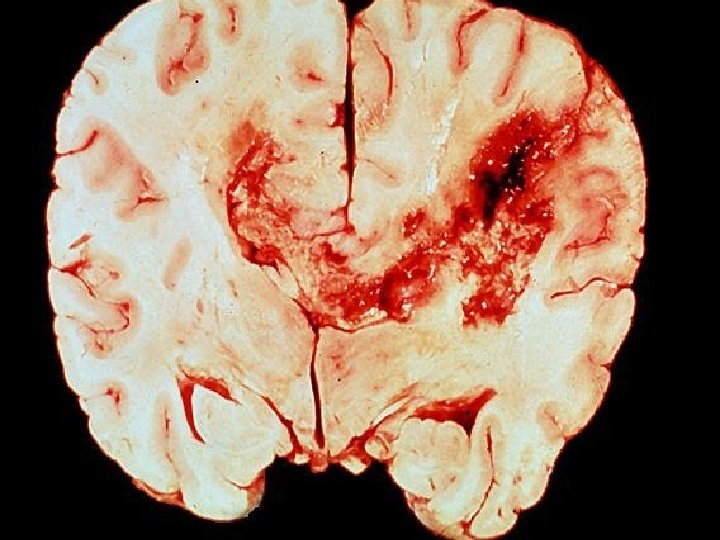

Heilahimnur � Heilahimnurnar (meninges) eru þrjár ◦ Yst er dura mater ◦ Í miðjunni er arachnoid mater �Undir henni er subarachnoid space þar sem margar stórar æðar liggja og heila- og mænuvökvinn er ◦ Pia mater er alveg límd við heilann og er örþunn ◦ Heilahimnubólga (meningitis) verður vegna bakteríu - eða vírussýkinga (örfá sinn vegna lyfja) ◦ Bakterían sem veldur hvað mestu tjórni nefnist Neisseria meningitidis. Þrátt fyrir sýklalyfjameðferð deyja um 10% og margir skaddast varanlega